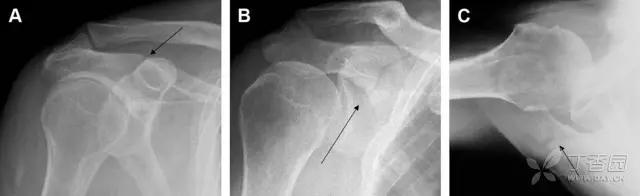

图 1 大结节骨折。(A)脂肪抑制序列斜冠状位 MRI,显示肱骨大结节线性骨折无移位(箭头)与周围骨水肿;(B)外旋位前后位(AP)片,证实大结节骨折(箭头),典型的骨折愈合过程中的骨吸收表现;(C、D)初诊时内旋位、外旋位前后位片,初诊时漏诊,仔细回顾影像,内旋伞下可见双密度影(椭圆),骨皮质中断(箭头)